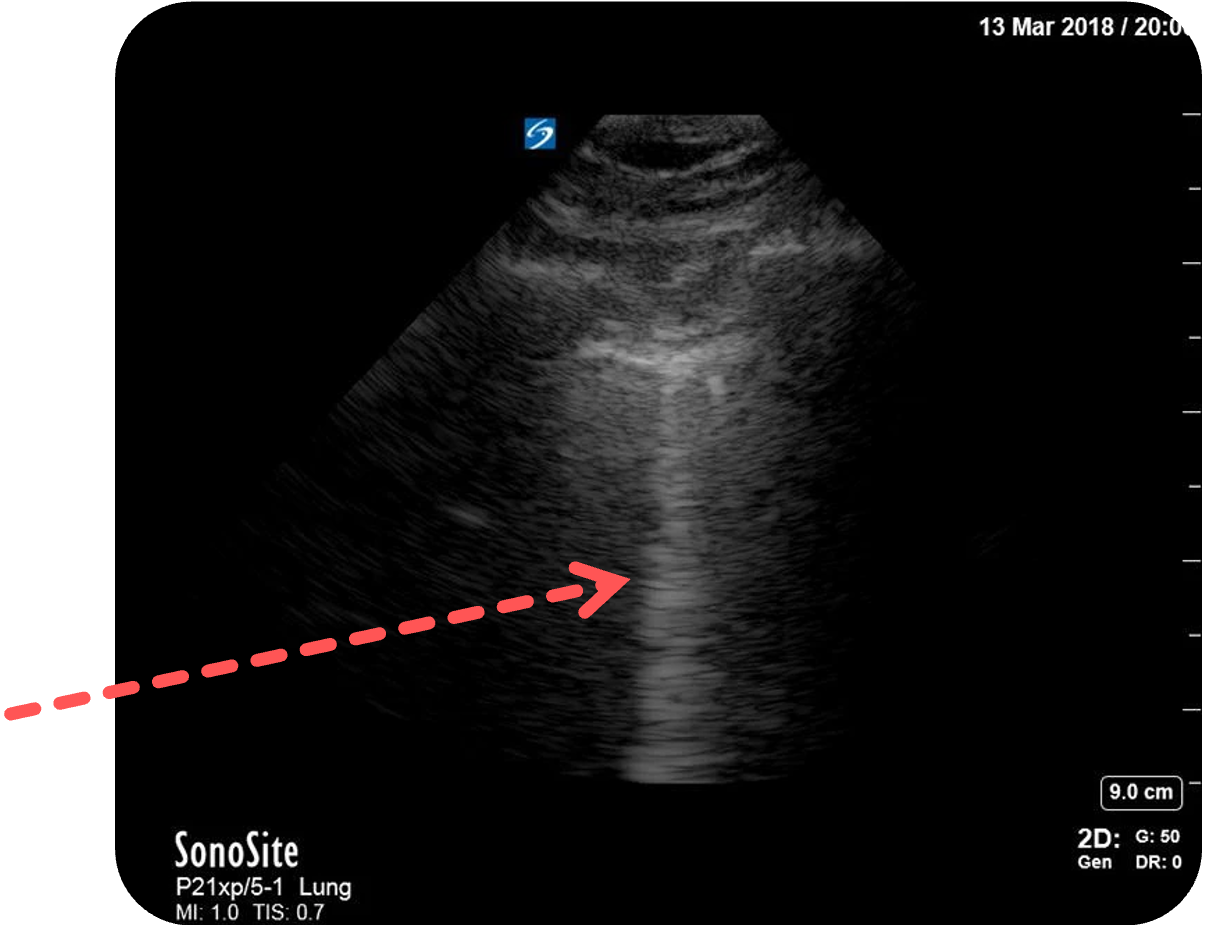

- Lungensliding: feines, horizontales Gleiten der viszeralen an der parietalen Pleura

- B-Lines: vertikale, bis zur Bildtiefe reichende Artefakte (kein Hinweis auf Pneumothorax

) (roter Pfeil)

Bildquelle: Figure 2 aus Ketelaars, R., Reijnders, G., van Geffen, GJ. et al. ABCDE of prehospital ultrasonography: a narrative review. Crit Ultrasound J 10, 17 (2018). https://doi.org/10.1186/s13089-018-0099-y. Teilausschnitt des Originalbilds. Der rote Pfeil wurde hinzugefügt.